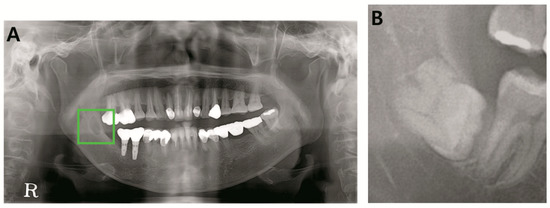

Dental strategies for osteoporosis drugs. Is a rare side effect however it is important that you know about it and take steps to protect your dental health. Other health conditions are arthritis diabetes and asthma. A recent two-day whirlwind trip to New York City left my head spinning as I sought to comprehend the complex world of prescribing behavior by physicians who write prescriptions for. A localized clinical approach eg treating a sextant at a time to dentoalveolar surgery in.

The authors discuss the current evidence regarding the risks of dental procedures in patients receiving IV bisphosphonates for this indication. Zoledronic Acid Zometa Reclast Author. They also evaluate important risk factors and the decision-making pathway in such cases. Last week while eating soft food fish and bread I broke the molar in half. HI thereI was actually waiting for the other shoe to drop and it kind of did.

A localized clinical approach eg treating a sextant at a time to dentoalveolar surgery in. So what happens if youre taking Fosamax or Prolia and you need dental work. I had an infusion with Reclast in August of 2010 and considering it again next month. But before having a more invasive proceduresuch as tooth extraction implant placement or oral. Her response to the medication was very uncomfortable and she never had another treatment done.

A 62 old year old female patient had one Reclast treatment zolendronic acid. Other health conditions are arthritis diabetes and asthma. The authors discuss the current evidence regarding the risks of dental procedures in patients receiving IV bisphosphonates for this indication. The study was divided randomly into two. Thats when I got the information about doing dental work prior to infusion.